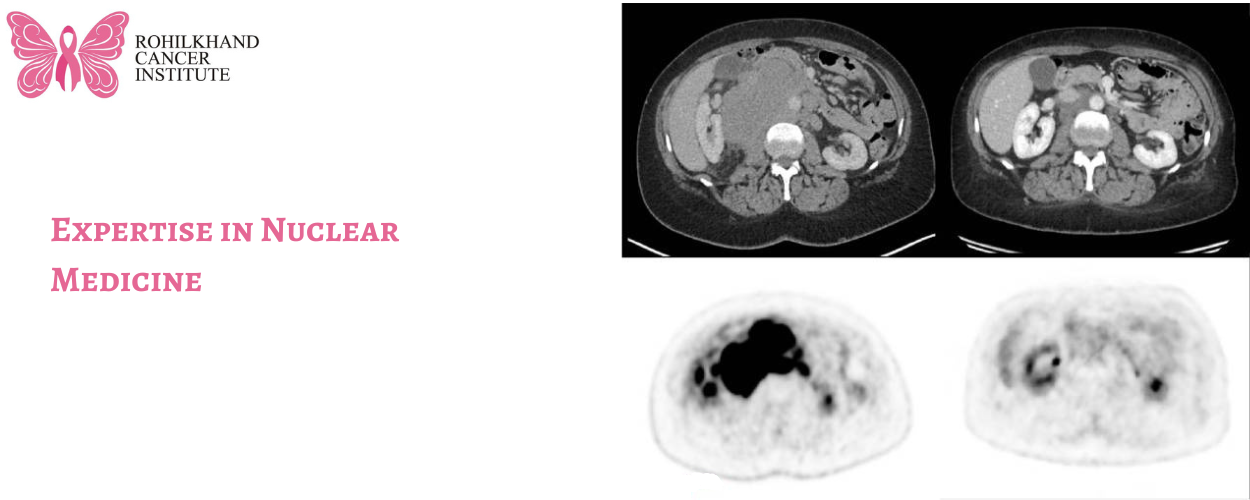

One of the cornerstone technologies in nuclear medicine is Positron Emission Tomography-Computed Tomography (PET-CT). This hybrid imaging technique combines the functional imaging capabilities of PET with the anatomical detail provided by CT scans. At Rohilkhand Cancer Institute, the PET-CT scan is instrumental in:

- Early Detection: Identifying cancerous cells at a molecular level before structural changes become apparent.

- Staging: Determining the extent of cancer spread within the body.

- Treatment Planning: Assisting in the formulation of personalized treatment strategies by providing detailed insights into tumor biology.

- Monitoring Response: Evaluating the effectiveness of ongoing treatments and making necessary adjustments.

- Detecting Recurrence: Identifying the return of cancer post-treatment.

The institute boasts a state-of-the-art GE 3-ring PET-CT scanner, the only one of its kind available between Delhi and Lucknow, covering an area of 200 km². This advanced technology ensures that patients receive accurate diagnoses and effective treatment plans.

Expertise in Nuclear Medicine

Leading the Department of Nuclear Medicine at Rohilkhand Cancer Institute is Dr. Ankit Kumar, a distinguished physician with extensive experience in the field. Dr. Kumar completed his MBBS at Maulana Azad Medical College, Delhi University, and his postgraduate studies in Nuclear Medicine at the Institute of Nuclear Medicine and Allied Sciences, Delhi University. His prior roles at esteemed institutions such as the Army Hospital Research and Referral, Rajiv Gandhi Cancer Institute, and Safdarjung Hospital in Delhi have equipped him with a wealth of knowledge and expertise. Since the institute’s inception, Dr. Kumar has been instrumental in establishing and advancing the nuclear medicine services offered, ensuring that patients have access to cutting-edge diagnostic and therapeutic options.